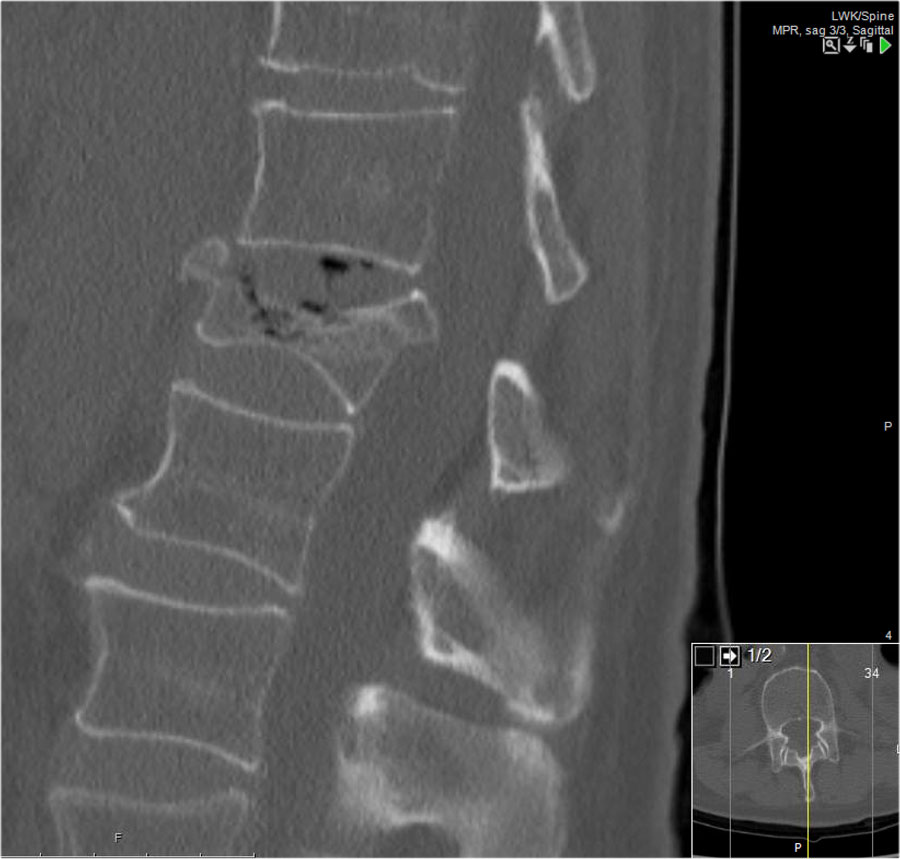

Gãy theo mặt phẳng đứng dọc của thân đốt sống và

cung sau đốt sống

Gãy theo mặt phẳng đứng dọc của thân đốt sống và gãy cung sau theo mặt phẳng đứng dọc gặp lần lượt trong 90% và 85% các trường hợp gãy vỡ.

Dưới đây là bốn ví dụ minh họa.

Trong phân loại Denis, đây sẽ là gãy ba cột — trước/giữa/sau — cho thấy gãy xương rất không vững.

Tuy nhiên, trong phân loại TLICS, đây là gãy vỡ, tức là 2 điểm cho hình thái.

Phương pháp điều trị sẽ phụ thuộc vào tính toàn vẹn của PLC và tình trạng thần kinh.